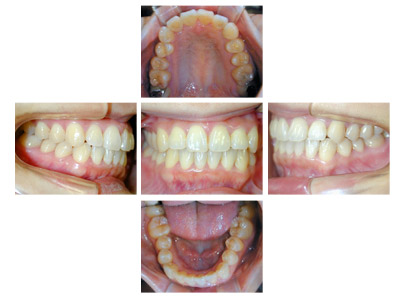

常滑市井戸田町在住 S.M様(23歳女性)

S.M様は口元の突出感と上顎前歯の傾きを主訴に当院の無料矯正相談にて来院されました。

来院当初より当院にて矯正治療をご希望されましたので通常通り模型採取、レントゲン撮影、口腔内写真の撮影、

正貌・側貌の撮影などの試料採取を行いました。

診断の結果、咬み合わせが骨格的には反対咬合傾向の上下顎前突である事や前歯上顎前歯の歯軸が左右方向に流れて傾斜していること、

咬み合わせが浅いことなど治療はやや難度の高いことをお話しいたしました。

前歯の咬み合わせが浅く切端咬合です。上顎前歯の歯軸が左右的に傾いています。

犬歯関係・臼歯関係ともにClass3です。

![]() |

犬歯関係、臼歯関係を咬み合わせが1歯対2歯のClass1に治療するためと口元の突出感を改善するために右側は上下顎第1小臼歯を抜歯しました。

左側は上顎第2小臼歯、下顎第1小臼歯を抜歯しました。

治療の経過で一時、反対咬合傾向がでましたが処置方針通り治療がすすみました。

S.M様は一度のキャンセルもなく予定通り来院治療され、

お渡ししてあった治療計画書通りに2年6ヶ月(30ヶ月)で動的治療を終えることができました。

治療期間:2年6ヶ月

治療費用:60万円